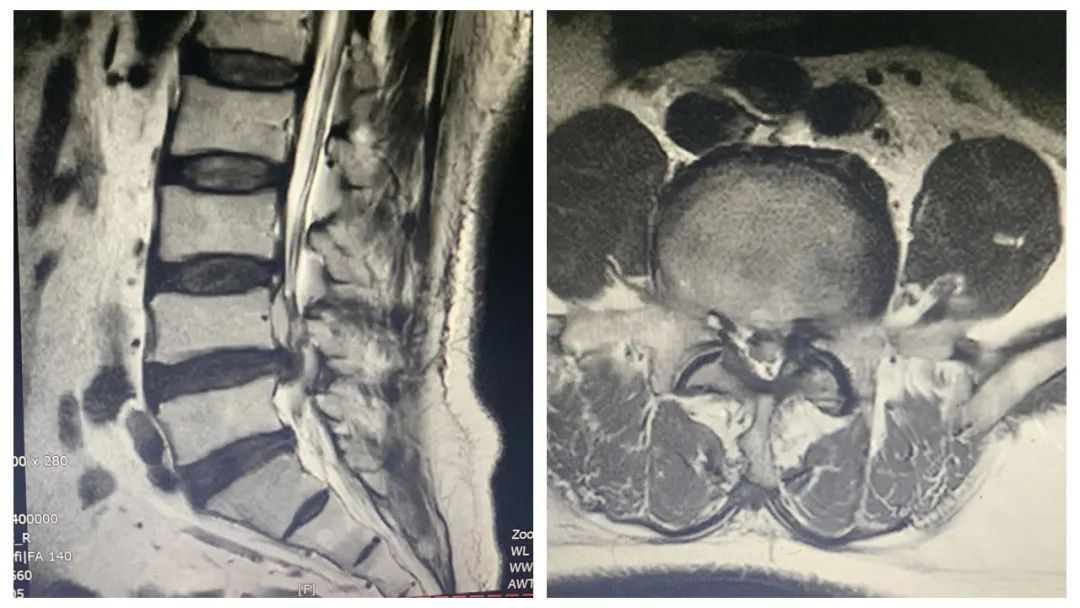

患者巫某,男性,72岁,因“腰痛伴左下肢放射痛、麻木20余天”入院。入院腰椎CT及MR检查示:腰4/5椎间盘突出,腰椎管狭窄。诊断:1、退变性腰椎管狭窄症 2、腰4/5椎间盘突出症。

影像学检查显示腰4/5椎间盘突出、腰椎管狭窄